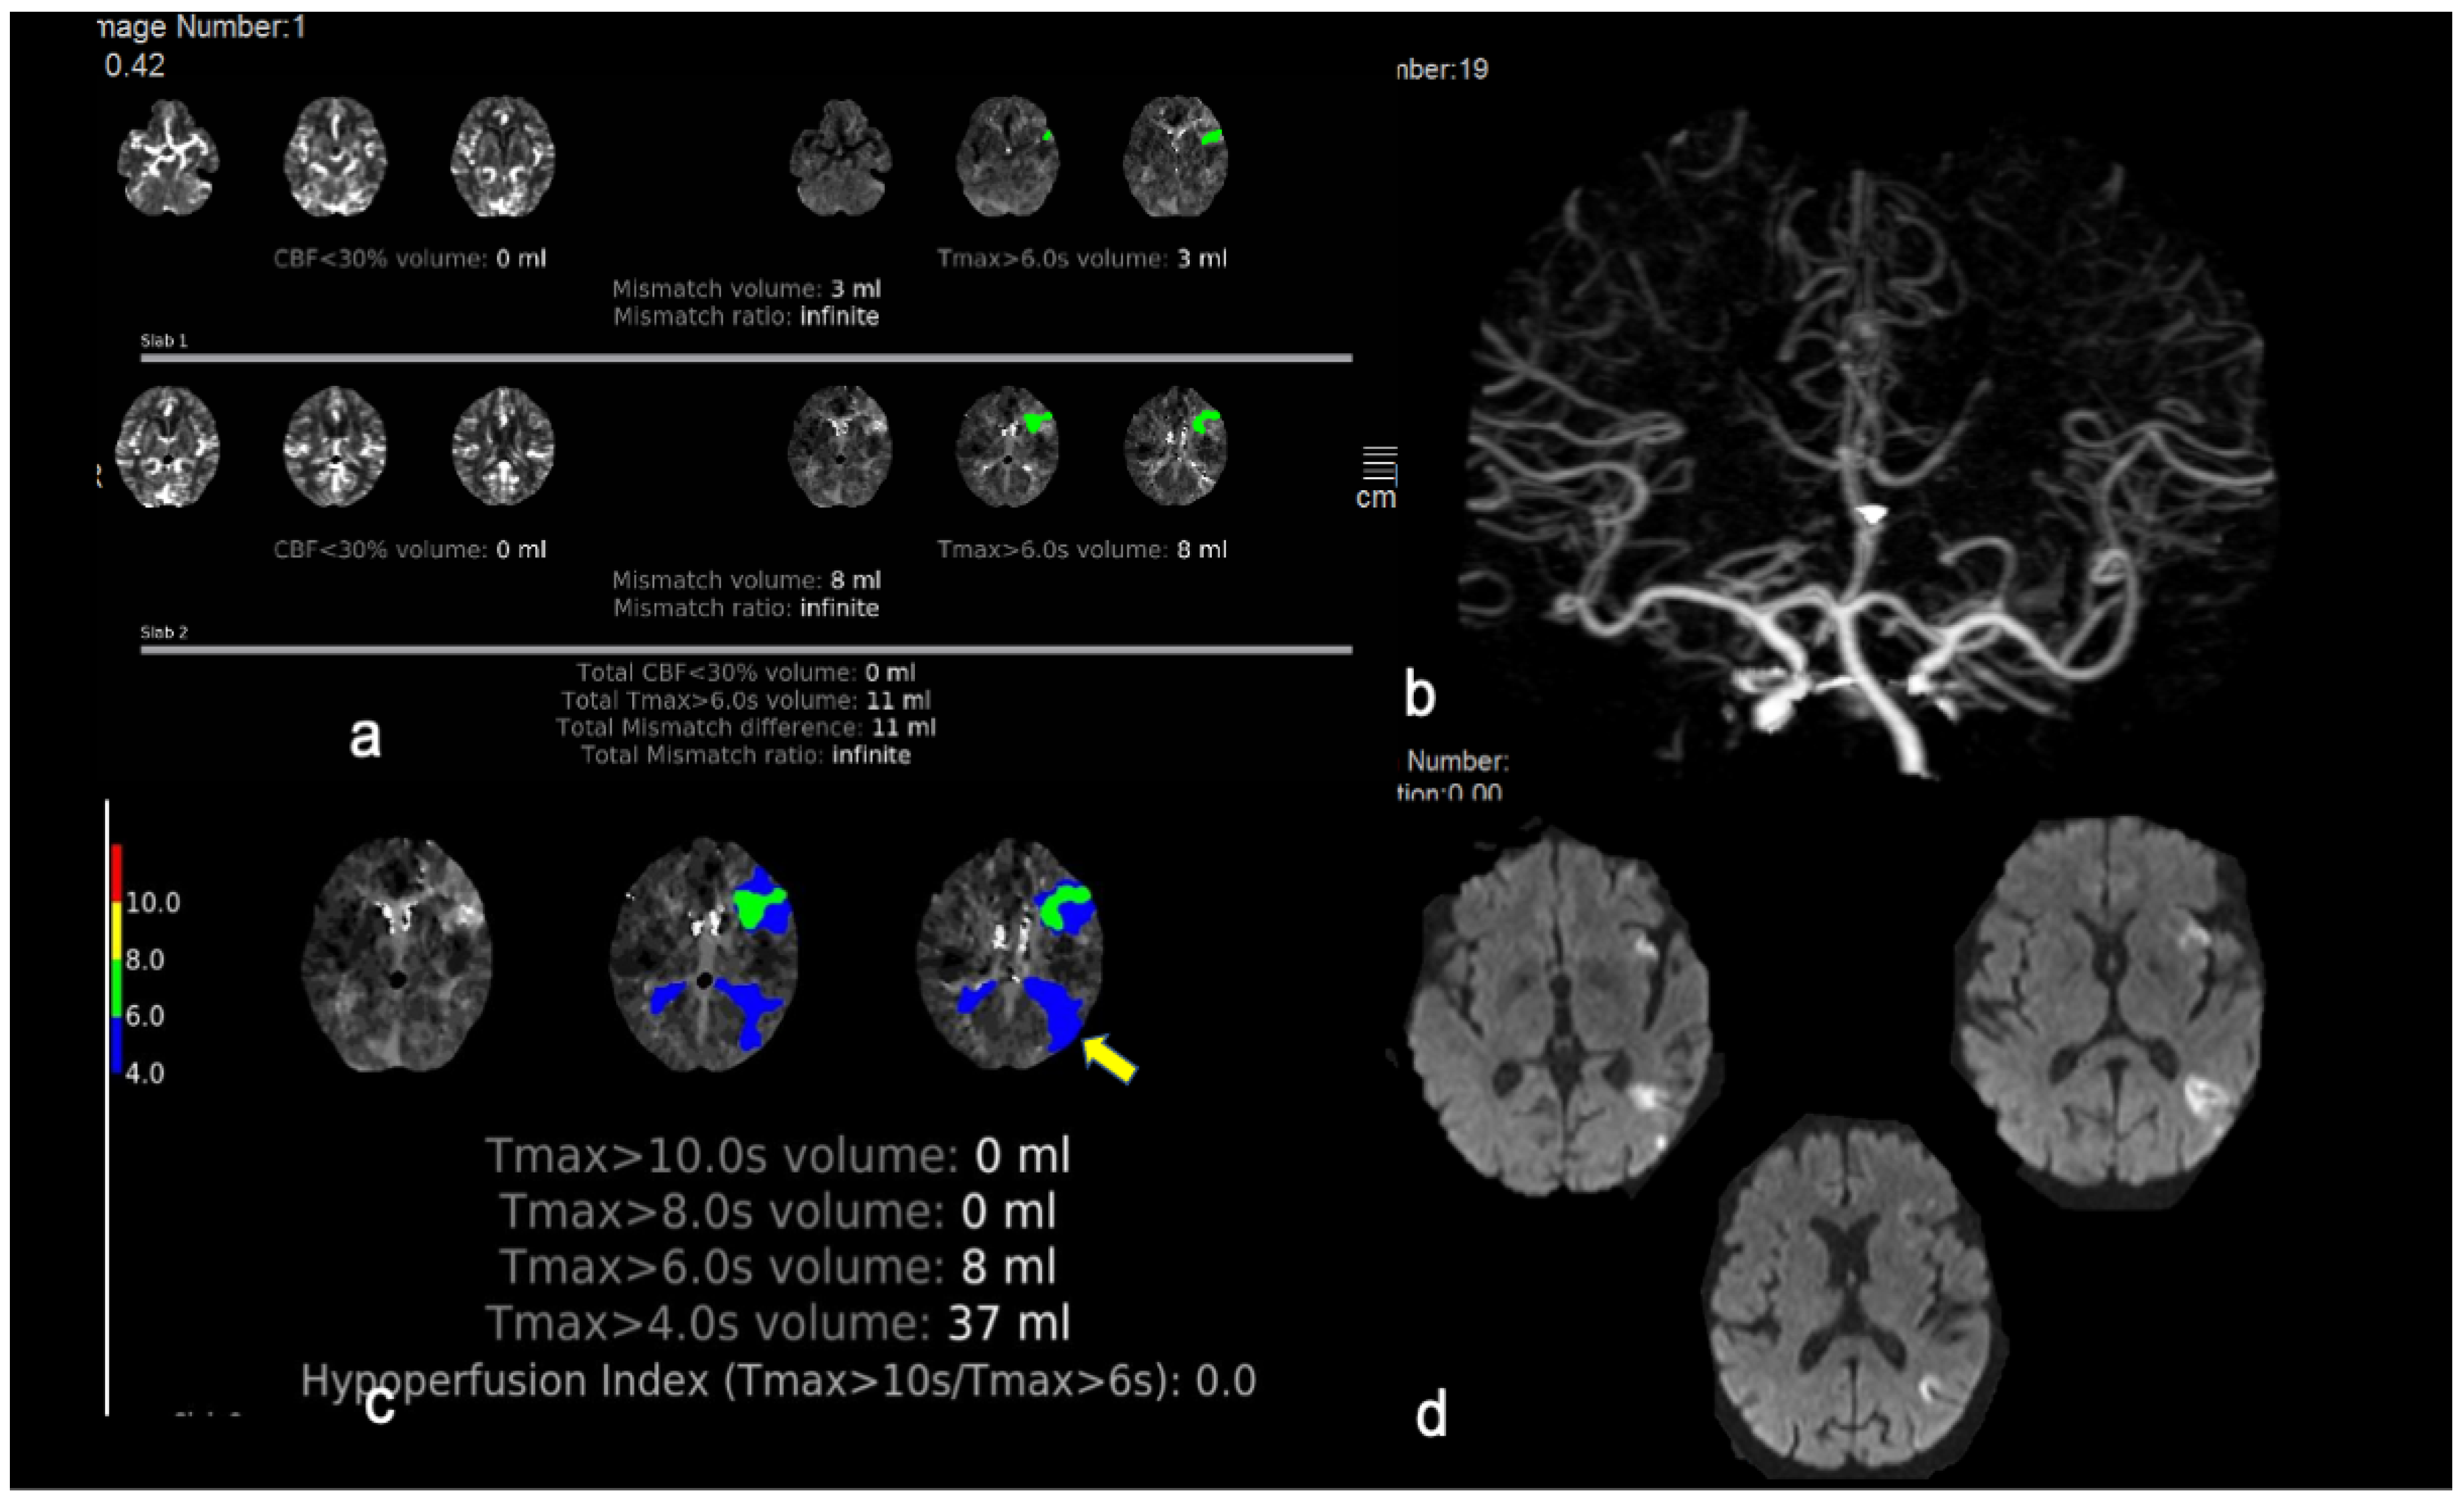

| Mean ischemic core volume (rCBF < 30%) (mean ± SD) (mL) | 2.1 ± 1.2 |

| Mean volume of critical hypo perfusion (Tmax > 6 s) (mean ± SD) (mL) | 16.3 ± 4 |

| Mean mismatch volume (mean ± SD) (mL) | 13.5 ± 3.3 |